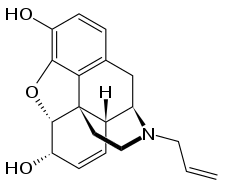

Buprenorphine Buprenorphine |

- Buprenorphine